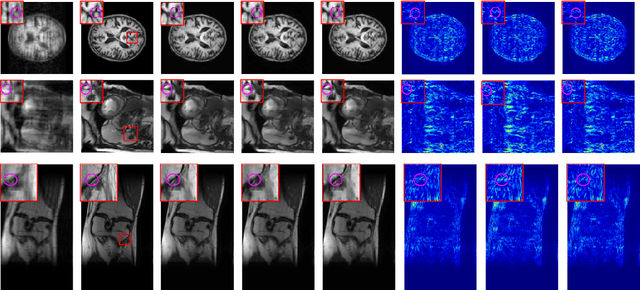

Abstract:Deep learning networks have shown promising results in fast magnetic resonance imaging (MRI) reconstruction. In our work, we develop deep networks to further improve the quantitative and the perceptual quality of reconstruction. To begin with, we propose reconsynergynet (RSN), a network that combines the complementary benefits of independently operating on both the image and the Fourier domain. For a single-coil acquisition, we introduce deep cascade RSN (DC-RSN), a cascade of RSN blocks interleaved with data fidelity (DF) units. Secondly, we improve the structure recovery of DC-RSN for T2 weighted Imaging (T2WI) through assistance of T1 weighted imaging (T1WI), a sequence with short acquisition time. T1 assistance is provided to DC-RSN through a gradient of log feature (GOLF) fusion. Furthermore, we propose perceptual refinement network (PRN) to refine the reconstructions for better visual information fidelity (VIF), a metric highly correlated to radiologists opinion on the image quality. Lastly, for multi-coil acquisition, we propose variable splitting RSN (VS-RSN), a deep cascade of blocks, each block containing RSN, multi-coil DF unit, and a weighted average module. We extensively validate our models DC-RSN and VS-RSN for single-coil and multi-coil acquisitions and report the state-of-the-art performance. We obtain a SSIM of 0.768, 0.923, 0.878 for knee single-coil-4x, multi-coil-4x, and multi-coil-8x in fastMRI. We also conduct experiments to demonstrate the efficacy of GOLF based T1 assistance and PRN.